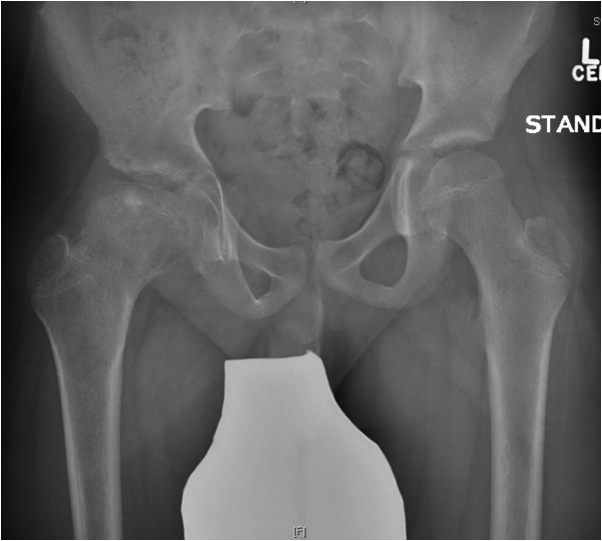

Xray

Grade stage of Perthes

Lateral Pillar classification

Chronological

- Waldenstrom

1. Initial

Duration : 3- 6 months

- may be normal

- small, sclerotic epiphysis

- joint space widening

- increased density of ossific nucleus & cessation of growth